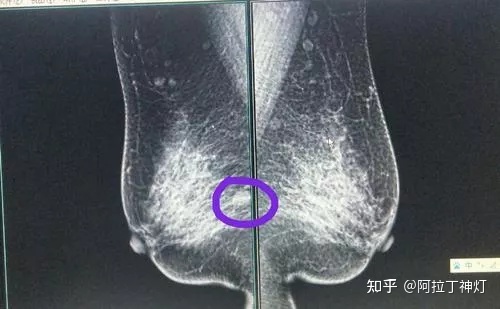

我觉得可能是我们当地的医疗水平不行这次干脆去省城治,西安的水平应该高一点,大夫的意思是吃药按摩外加烤电治疗。本来以为省城能治好,结果烤电坚持了1个多月不用检查我都知道没啥效果,硬块自己还是能摸到那么大,省城的老师说做好再次手术的准备。下面这张图是2021年2月烤电加按摩期间的检查单。

(2021年2月烤电的检查单)